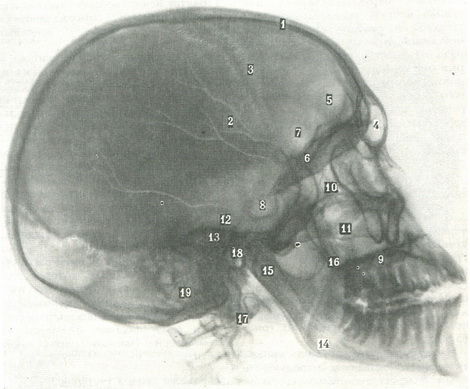

66. Бічна оглядова рентгенограма черепа (по Л. Д. Линденбратену).

1 - вінцевий шов: 2 - гілки середньої менингеальной артерії, 3 - ламбдовідного шов; 4 - лобова пазуха; 5 - дно бічних відділів передньої черепної ямки; 6 - основна пластинка; 7 - дно середнього відділу передньої черепної ямки; 8 - турецьке сідло; 9 - вилична кістка; 10 - клітини гратчастого лабіринту; 11 - верхньощелепні пазухи; 12 - дно бічних відділів середньої черепної ямки; 13 - піраміди скроневих кісток; 14 - кут нижньої щелепи; 15 - мищелковий відросток нижньої щелепи; 16 - вінцевий відросток нижньої щелепи; 17 - зуб II хребця; 18 - отвір зовнішнього слухового проходу; 19 - клітин соскоподібного відростка.